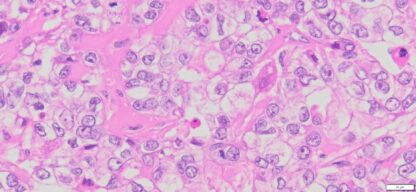

Description

| Organ& Tissue | Pathology Diagnosis | Gender/Age | % Tumor Area | Grade | TMN Stage | IHC Biomarkers |

| Human Ovary | Ovarian clear-cell carcinoma or ovarian clear-cell adenocarcinoma | Female/67 | 80% | II | pT1aNxMx | ER(-),PR(-),Pax8 (+),WT1(-),p53(-),Ki67(70%) |

Human tissue was fixed in formalin immediately after excision and embedded in paraffin. The tissue sections were 5 µm in thickness and mounted each on positively charged glass slides.